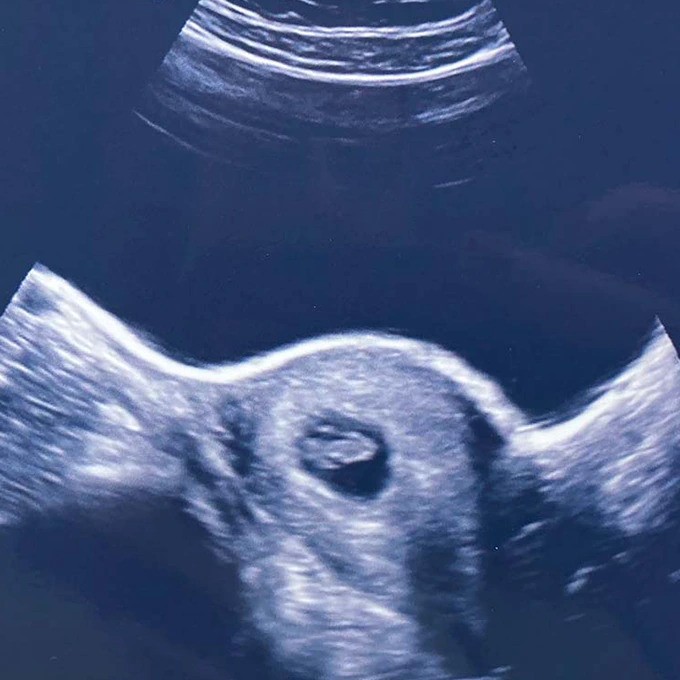

At 7 weeks pregnant, we booked an appointment at a private baby scanning studio. We were travelling to see close friends that weekend and knew we wanted to tell them but wanted some reassurance first. Part of me still thought I was dreaming!

We were warned that with such an early scan, there was a high chance we wouldn’t be able to see anything. I drank gallons of water to give us our best shot and sure enough, there was a tiny little blob with a strong heartbeat. Our hearts melted as we stared at the screen, somehow in shock and awe all over again.

Before falling pregnant, I had booked a week in Ibiza with friends. Luckily, this fell just after 12 weeks so we felt it was safe enough to travel. My first scan with the NHS didn’t fall until after the holiday when I would be almost 14 weeks, so we decided to book another private scan before I went away.

At just short of 12 weeks pregnant, we could now see the most perfect little baby. No longer a little blob, but a tiny little person kicking their arms and legs. Suddenly the last few weeks of feeling horrendous all seemed more than worth it. I burst into tears of relief and love, we’ll never forget that moment.